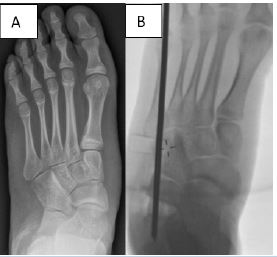

CLO was performed using the established surgical technique described by Mosca [17], (Figure 2A & B). At the conclusion of the procedure, a below-knee plaster of Paris splint was applied. At the first outpatient follow-up visit, 2 weeks postoperatively, the splint was converted to a circular plaster of Paris cast and maintained for an additional 4 weeks.

Figure 2: Pre-operative radiograph (A); Calcaneal lengthening osteotomy with corrected talo-navicular coverage (B).